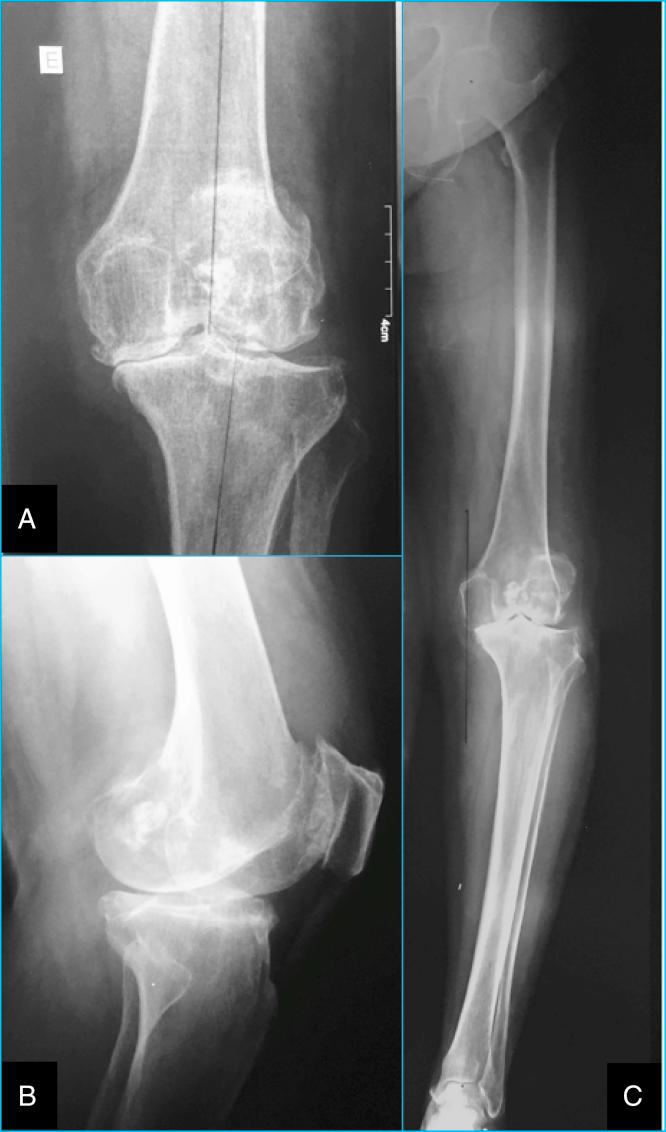

For decades, the main cause of failure in total knee arthroplasty (TKA) is still the malalignment of prosthetic components. The authors present a case of advanced knee arthrosis, treated by TKA. Preoperative planning was performed with a mobile application and the patient was submitted to primary TKA using an implant developed with inspiration from the theory of "modified GAP" with a rotated tibial tray. Neutral mechanical alignment of the lower limbs was obtained and the application proved to be viable regarding its proposed plan for this case.

几十年来,全膝关节置换术(TKA)失败的主要原因仍然是假体组件排列不齐。作者介绍了一例晚期膝关节骨性关节炎患者,采用TKA进行治疗。术前使用移动应用程序进行规划,并使用一款受“改良GAP”理论启发开发的带有旋转胫骨托的植入物对患者实施初次TKA。实现了下肢的中立机械对线,并且该应用程序在针对此病例的拟议计划方面被证明是可行的。